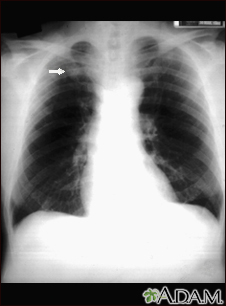

Pulmonary nodule - front view chest x-ray

This x-ray shows a single lesion (pulmonary nodule) in the upper right lung (seen as a light area on the left side of the picture). The nodule has distinct borders (well-defined) and is uniform in density. Tuberculosis (TB) and other diseases can cause this type of lesion.